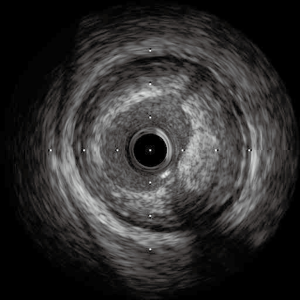

Over the decades, IVUS has been used as a primary invasive tool for coronary plaque assessment, utilizing its superiority over coronary luminography (i.e., coronary angiography). With an axial resolution of 150 to 250 µm and a lateral resolution of 250 µm, several findings of vulnerability have been identified (Figures 2,3). In addition to conventional grayscale IVUS, new generation of IVUS are available. Virtual histology (VH)-IVUS uses auto regression model to generate spectral parameters for the backscattered signal which are then color coded (Figure 2), whereas integrated backscatter (IB)-IVUS uses Fast Fourier Transformation to analyze the radiofrequency backscatter and create a color map. Given the inherent limitations placed on IVUS by its spatial resolution, a necrotic core >10% without evident overlying fibrous tissue and a plaque volume of >40% is required as a surrogate for thin-cap fibroatheroma (TCFA) (53). IVUS elastography and palpography have also been used to characterize the stress strain relationship on coronary arteries and plaques.

OCT has been used initially in ophthalmology and is now clinically available in cardiology. Compared with IVUS, OCT offers more precise assessment of coronary plaques, utilizing a 10-time greater resolution than that of IVUS (a spatial resolution of 10 µm axially and 20−40 µm laterally). OCT enables the visualization of several important plaque features assisting in determining plaque vulnerability: TCFA, plaque rupture, plaque erosion, lipid core, micro-calcification and neo-vascularization. The description of TCFA incorporates a fibrous cap <70 µm and also requires the arc of the lipid pool to subtend an angle >90 degrees in certain trials as seen in Figure 4. However, there is no strict definition of TCFA and a consensus statement rather ambiguously suggested, OCT-TCFA should reflect the histological definition of a TCFA (61).